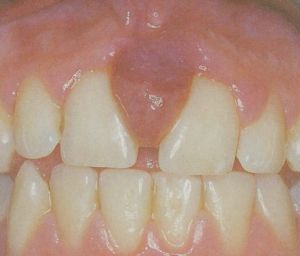

妊娠型牙齦瘤牙齦瘤以女性患者多見,中青年發病較多。多發生於唇頰側齦乳頭,以雙尖牙區最常見,舌、齶處少見,一般為單個牙發生。腫塊較局限,大小不一,通常呈圓形、橢圓形,有時為分頁狀,有的有蒂如息肉狀,有的無蒂基底寬廣。血管型和肉芽腫型者質地柔軟、色紅;纖維型者質地較韌且硬,顏色粉紅。腫塊一般生長緩慢,但在女性妊娠期可迅速增大。腫塊長大可以遮蓋部分牙面及牙槽突,表面可見牙壓痕,易被咬傷而發生潰瘍、出血或伴發感染。一般無痛,腫物表面發生潰瘍時可感覺疼痛。長期存在的較大腫塊可以壓迫並破壞牙槽骨壁X線示局部牙周膜增寬,致使牙鬆動、移位。